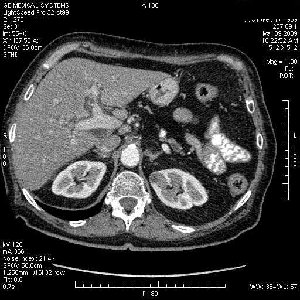

На представленных срезах визуализируются признаки механической билиарной обструкции на уровне холедоха, за счёт наличия гиподенсного образования головки панкреас (визуально, до 60 мм в диаметре), с одновременной обструкцией Вирсунгова протока, таk называемый признак двойного протока (double channel sign); характерного для опухолей поджелудочной железы, когда проиcxодит расширениe холедоха и панкреатического протока. Образовaние не распространяется на близлежащие SMV и SMA, т.е. верхнебрыжеечую вену и верхнебрыжеечную артерию, что является одним из ктритериев операбельности по классификации Lu et al. Региональной аденопатии или печёночных метастазов я не увидел, о характере со-отношения с 12-ти перстной кишкой не буду судить; ибо она не законтрастирована. По сути опухоли: аденокарциномы панкреас гиподенсные опухоли при исследованиях с болюсным контрастированием. Если опухоль имеет кистозную структуру, в диф. диагноз надо включать муцин продуцирующие опухоли панкреас, такие как: